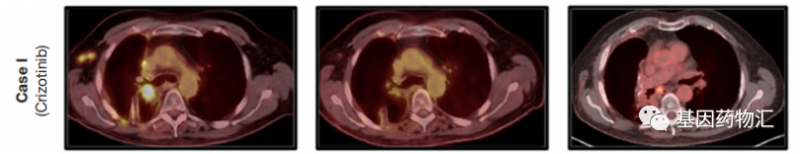

他一线使用了克唑替尼治疗,以及针对骨转移的放疗等处理措施。3个月后复查的MRI显示,R先生的脑内出现了17个转移病灶!

克唑替尼本身的入脑活性并不理想,R先生只能继续接受脑部的放疗(射波刀)来消除脑部病灶,并继续使用克唑替尼控制身体其他部位的肿瘤。整体来说疗效不错,病灶有比较明显的缩小。

然而,在克唑替尼治疗14个月后,R先生脑部的MRI扫描再次提示,出现了超过40个新的微转移病灶!

但是此时R先生的进展部位只有脑,身体其他部位的病灶仍然与之前相比有缩小,因此他换用了与克唑替尼同为第一代ROS1抑制剂、但治疗脑转移病灶效果更好的恩曲替尼。